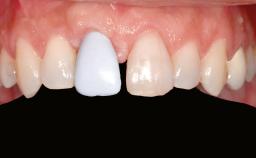

Shell Technique for Horizontal and Vertical Maxillary Bone Augmentation in a Partially Edentulous Patient with Aggressive Periodontal Disease

Prosthesis Type FDP